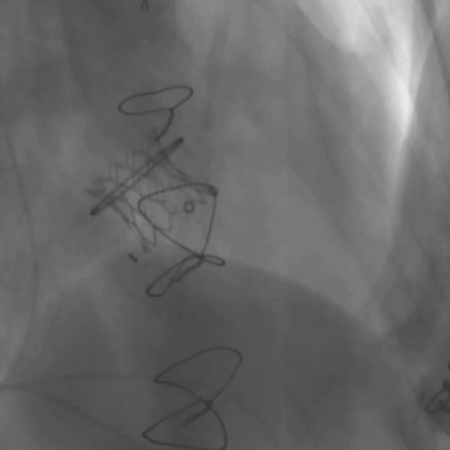

瓣中瓣植入后无反流及瓣周漏

术前经详尽评估患者病情,通过CT重建测量瓣环直径、左室流出道面积。结合之前外科换瓣手术入路,决定采用经心尖途径行二尖瓣“瓣中瓣”手术。术中选用25# Renato®球扩式瓣中瓣,顺利通过心尖途径植入。手术过程顺利,几乎无出血。最终瓣中瓣植入位置理想,功能表现出色,左室造影及经食道超声观察无明显瓣中及瓣周反流。二尖瓣峰值流速由术前2.5m/s降至1.5m/s,平均跨瓣压差由11mmHg降至2.6mmHg。